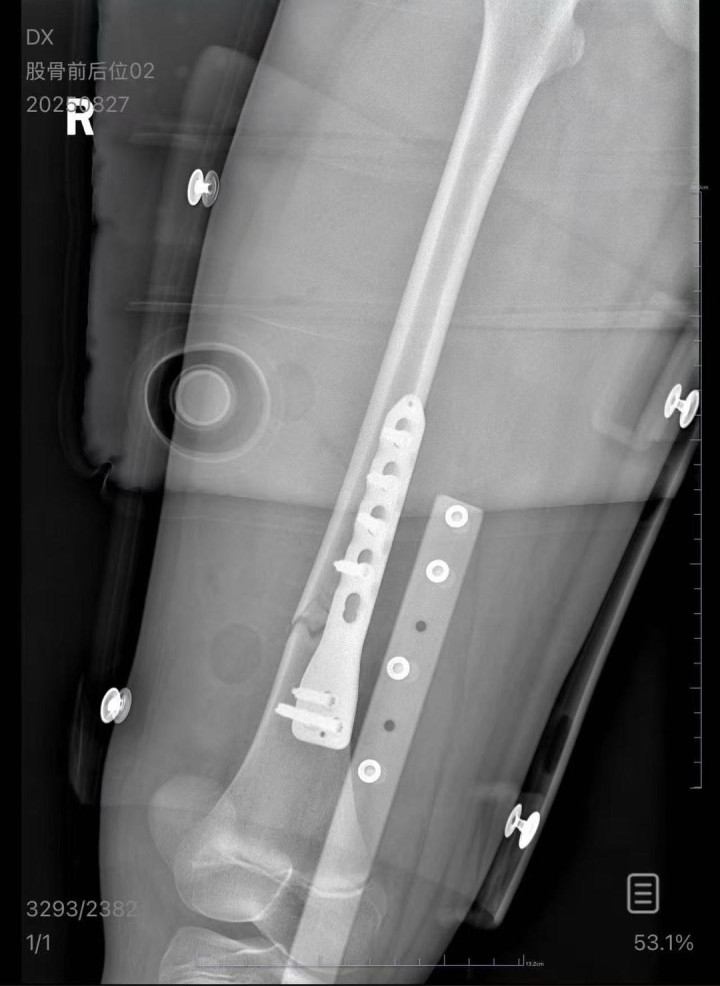

朱女士向记者出示的医院病历显示,8月24日凌晨,朱女士的女儿到医院就诊。医院诊断朱女士的女儿右股骨骨折,需要住院进一步治疗。

▲朱女士女儿手术后拍的X光片受访者供图